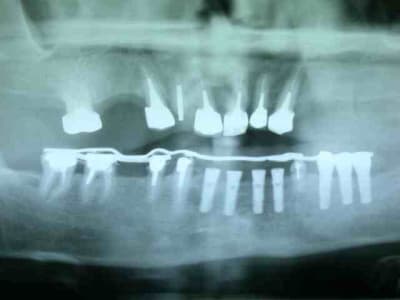

moulage panoramique...

bon allez je vous mets la pano initial et je continue après.